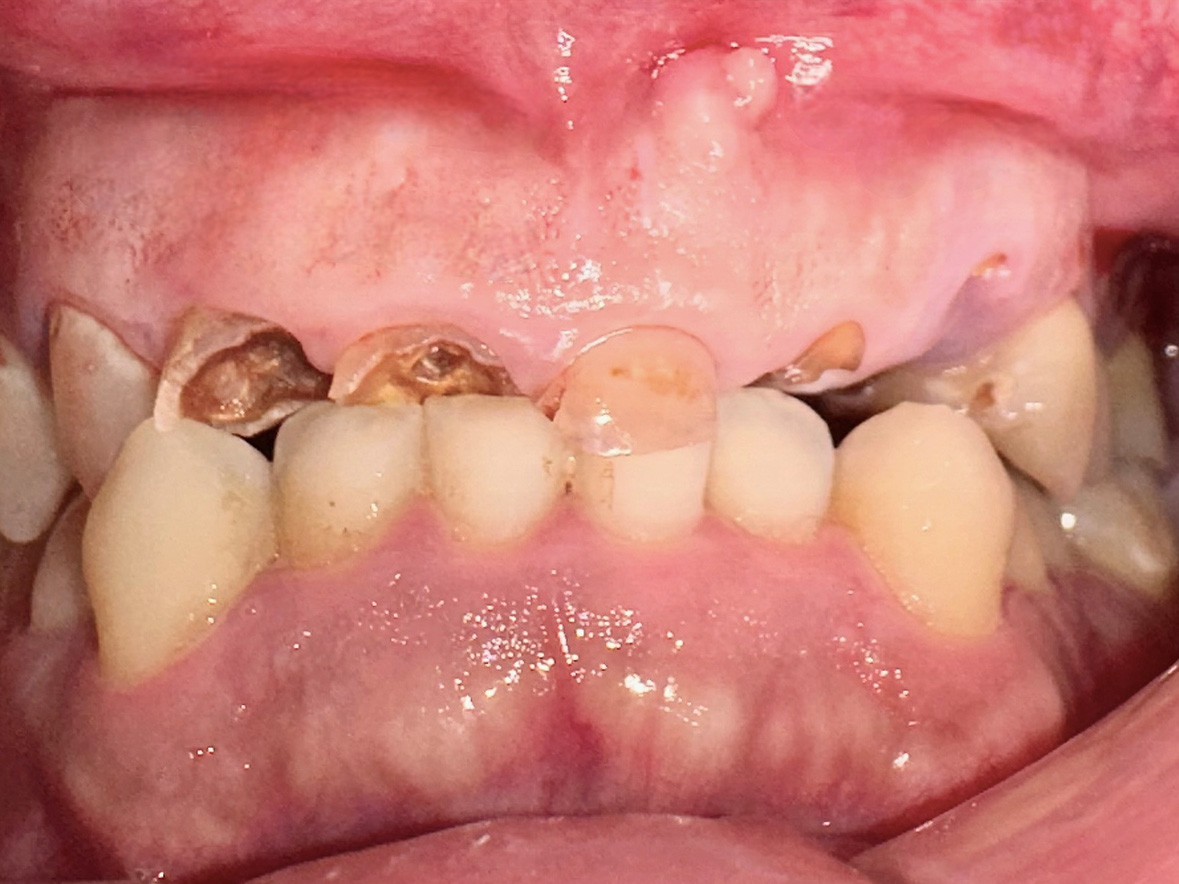

症例2

患者様の年齢 70代女性 主訴 入れ歯が痛い 噛みにくい 治療内容 上顎オールオン6

下顎臼歯部3本インプラント治療

抜歯即時インプラント埋入後3ヶ月の待機期間後、ジルコニアによる上部構造装着費用 456万円 治療期間・通院回数 6ヶ月/8回 デメリット・リスク 外科処置に伴う痛み・腫れ・出血・合併症の可能性があります。 -